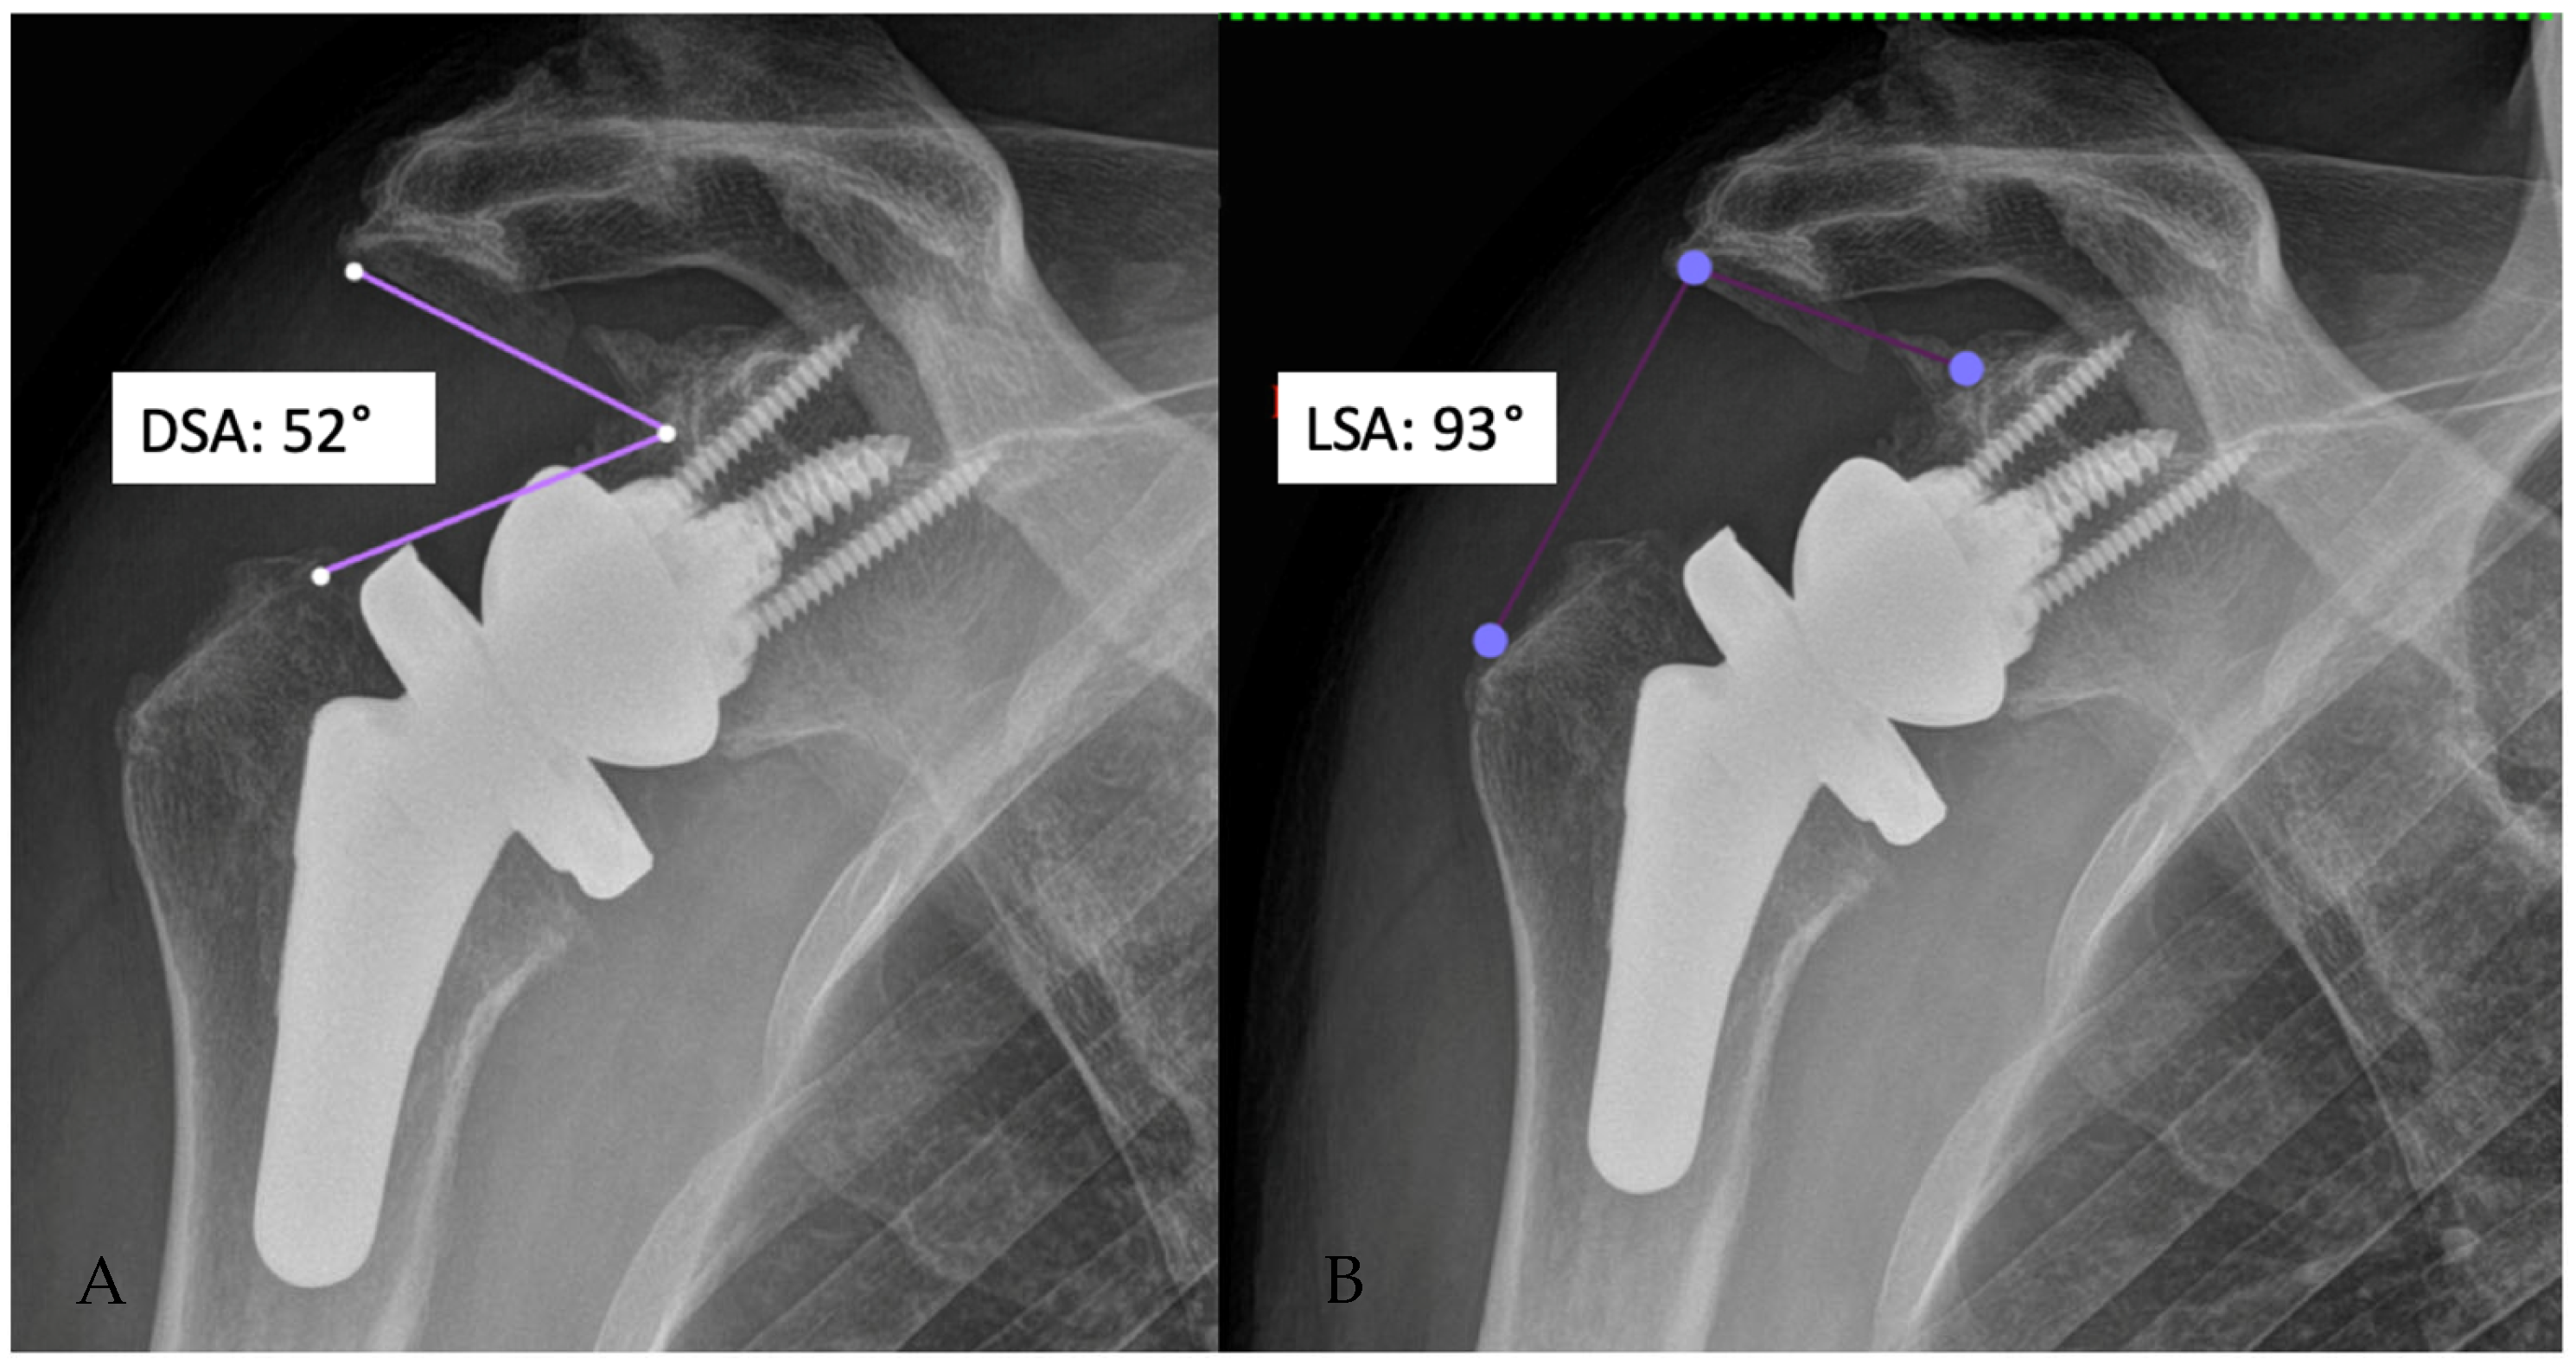

5. Radiographic Features of Lateralized Reverse Arthroplasty

- Boutsiadis, A.; Lenoir, H.; Denard, P.J.; Panisset, J.-C.; Brossard, P.; Delsol, P.; Guichard, F.; Barth, J. The Lateralization and Distalization Shoulder Angles Are Important Determinants of Clinical Outcomes in Reverse Shoulder Arthroplasty. J. Shoulder Elb. Surg. 2018, 27, 1226–1234. [Google Scholar] [CrossRef] [PubMed]